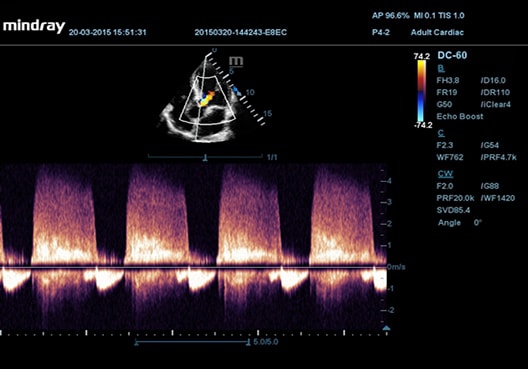

• Echo Boost™ - режим улучшенной визуализации для кардиологии

• Stress Echo - пакет для проведения и оценки результатов стресс-эхокардиографии (необходим Physio Module)

• Секторный фазированный датчик Mindray P4-2